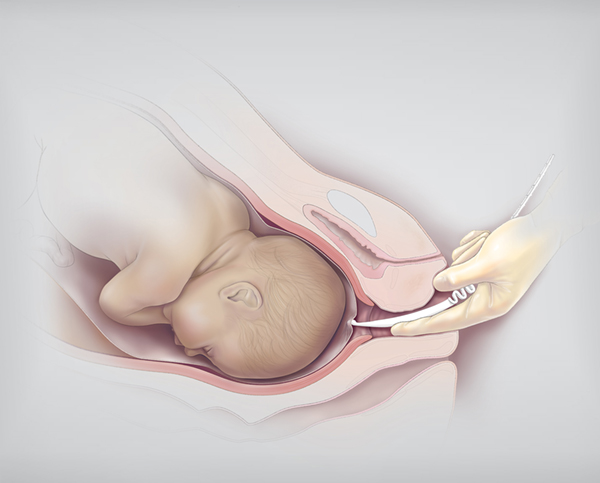

Околоплодный пузырь и плацента: структура и функции